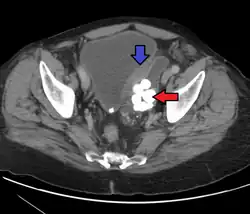

Transitional cell carcinoma is a type of cancer that arises from the transitional epithelium, a tissue lining the inner surface of these hollow organs.[1] It typically occurs in the urothelium of the urinary system; in that case, it is also called urothelial carcinoma. It is the most common type of bladder cancer and cancer of the ureter, urethra, and urachus. Symptoms of urothelial carcinoma in the bladder include hematuria (blood in the urine). Diagnosis includes urine analysis and imaging of the urinary tract (cystoscopy).

It accounts for 95% of bladder cancer cases and bladder cancer is in the top 10 most common malignancy disease in the world and is associated with approximately 200,000 deaths per year in the United States alone.[2][3] It is the second most common type of kidney cancer, but accounts for only five to 10 percent of all primary renal malignant tumors.[4] Men and older people have a higher rate of urothelial carcinomas. Other risk factors include smoking and exposure to aromatic amines.[5]